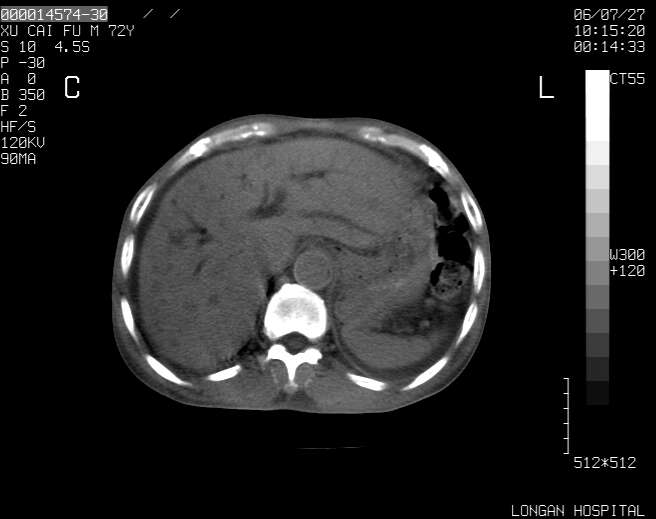

以下是引用winter在2006-7-30 20:14:00的发言:[br]1、考虑胆囊癌伴胆道侵犯并高位胆道梗阻、肝内多发转移、腹膜后淋巴结转移。[br]2、右肾轻度积水。[br]3、老人家72岁了胰腺头体尾部均较饱满,不过未见密度异常及其他异常征象。[br]4、腹水。

以下是引用jiajie在2006-7-31 7:10:00的发言:[br]考虑肝转移瘤,腹膜后淋巴结增大。[br]胃癌不能除外,建议胃镜检查。